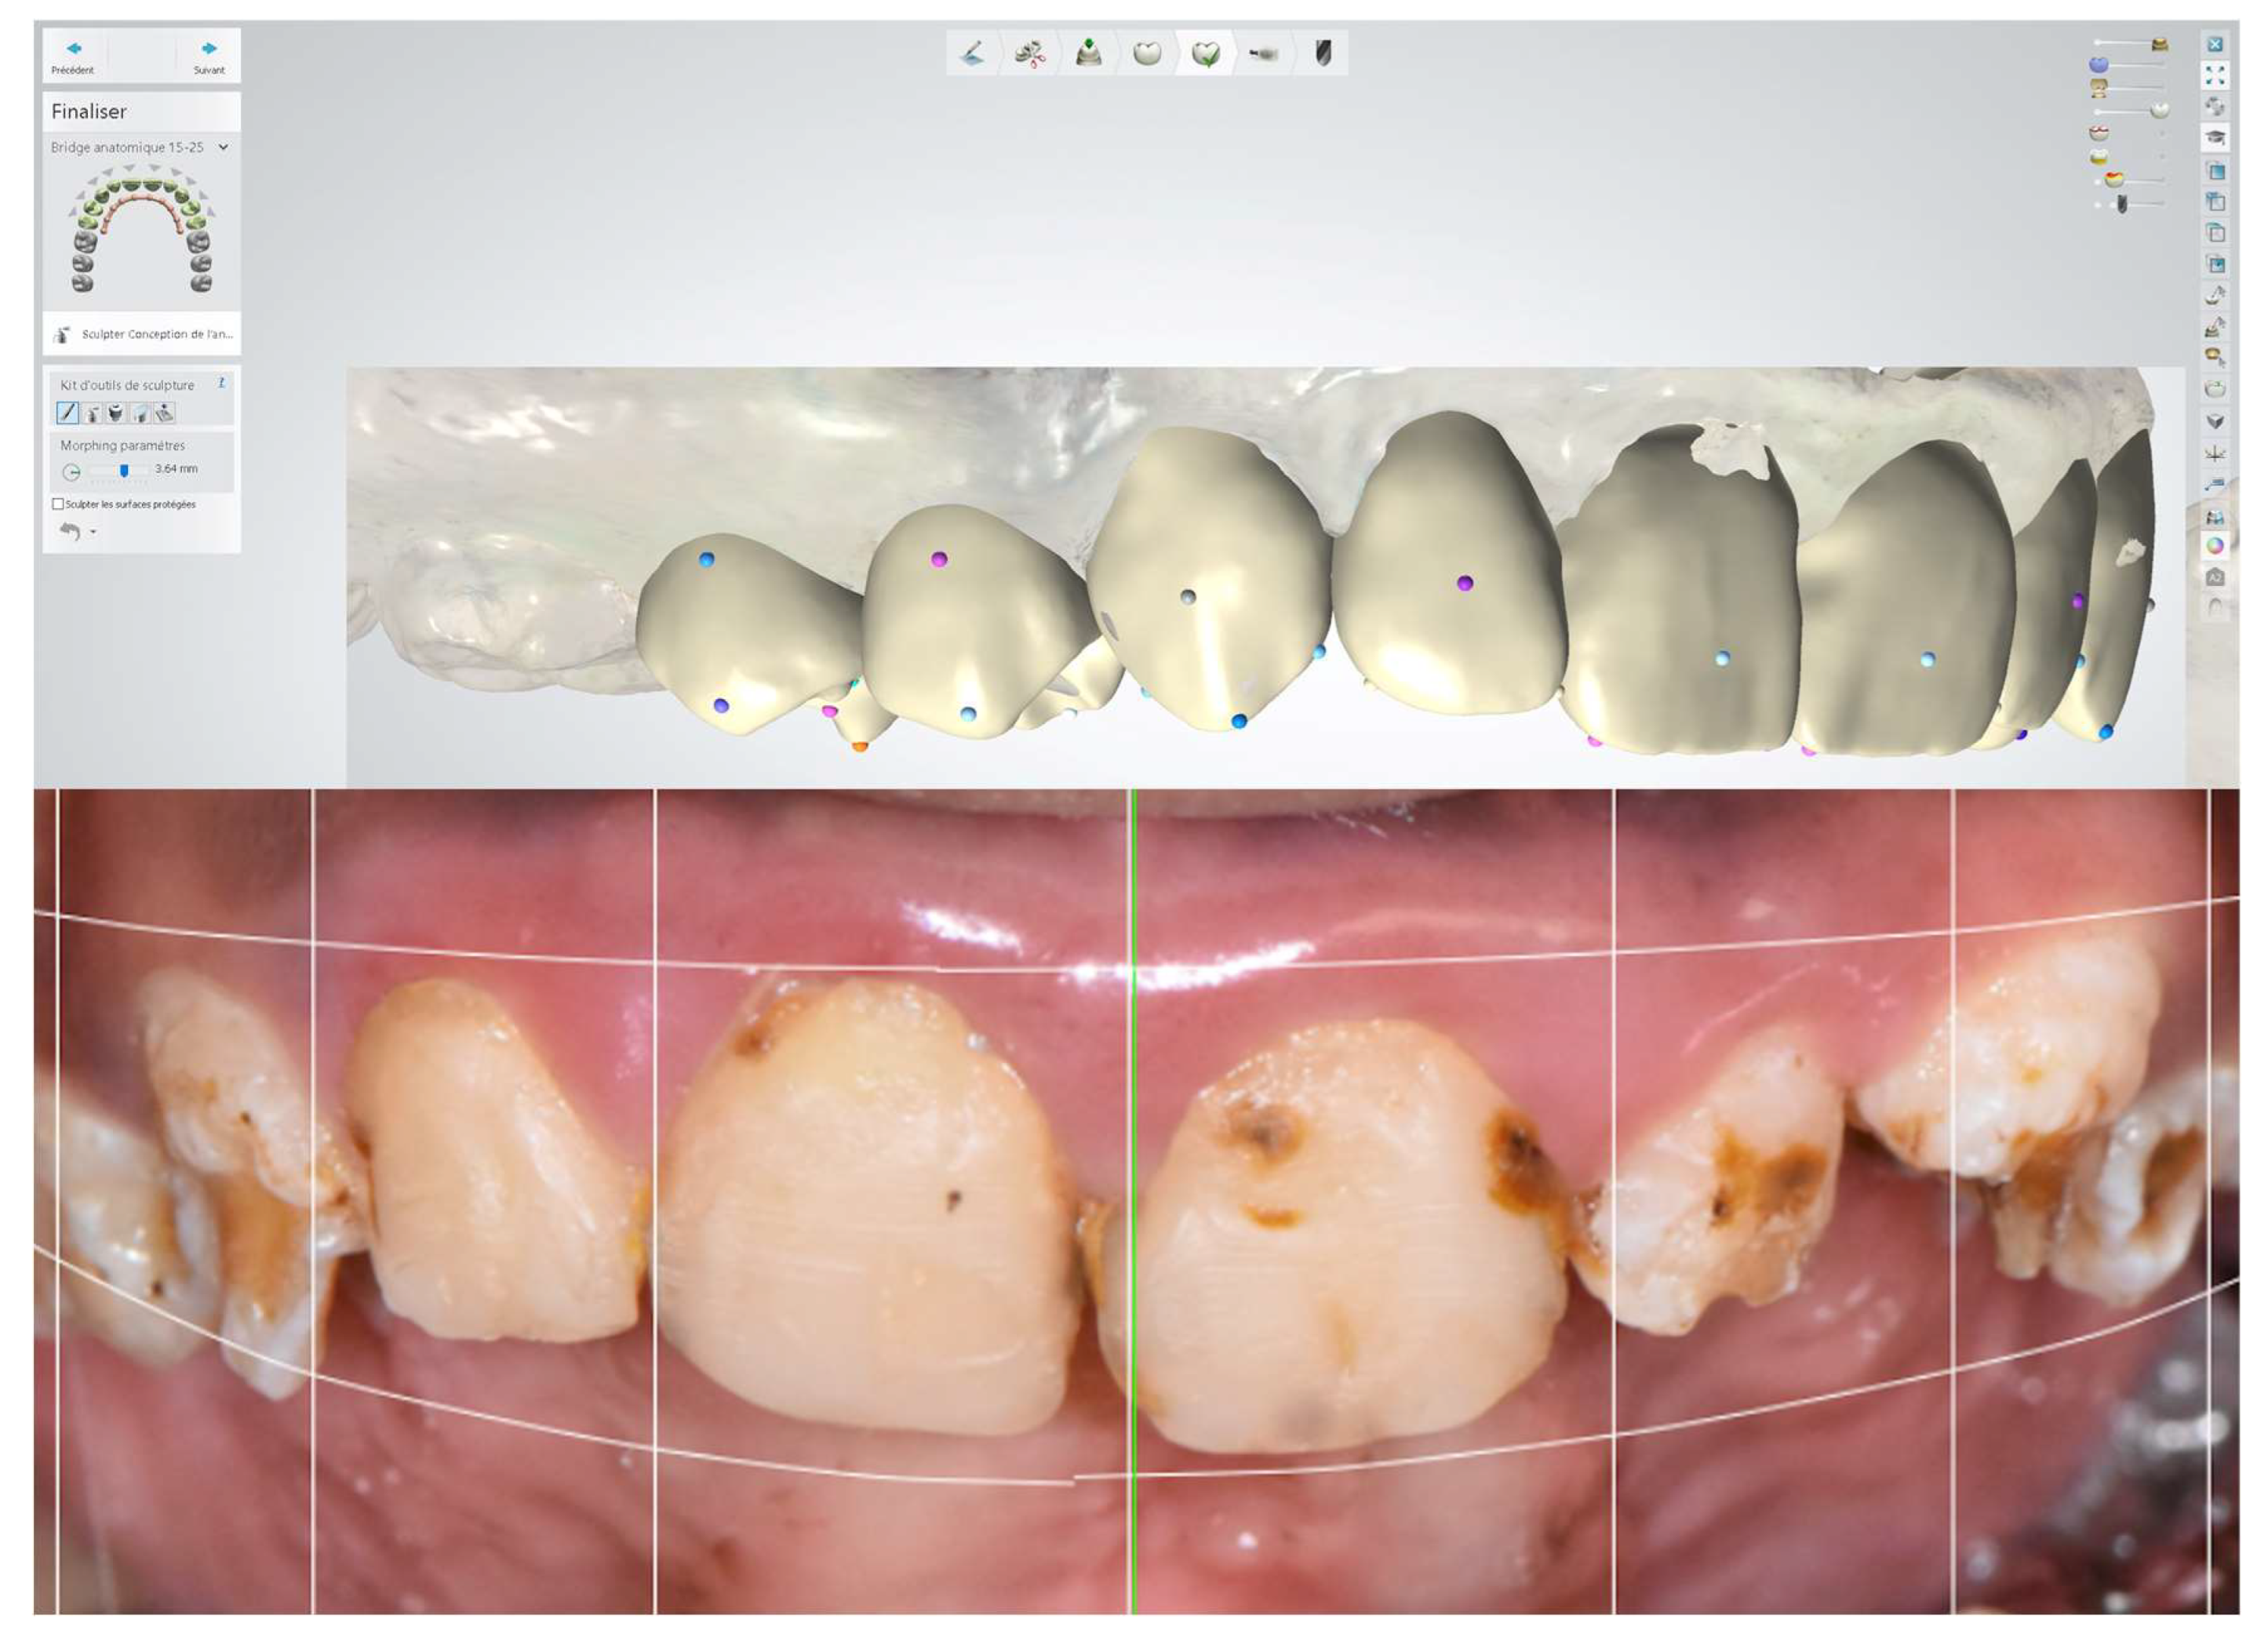

2.10. Rehabilitation of the Maxillary Second Right Premolars to Maxillary Second Left Premolars

2.10.1. Sixth Session (Mock-Up Session)

2.10.2. Seventh Session (Tooth Preparation)

3.2. Digital Wax-Up and Use of CAD-CAM